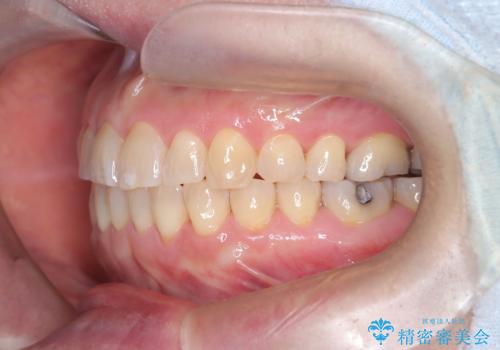

前歯の軽度なガタつきを、1年で美しく整える審美ワイヤー矯正

- 前歯の軽度なガタつき(叢生)を気にされてご来院されました。精密な検査の結果、抜歯は不要で、わずかなスペースを確保することで歯並びを整えられると診断。患者様のご希望と状態に合わせ、目立ちにくい審美ブラケットを使用したワイヤー矯正による治療計画を立案しました。スペース確保は、奥歯を少し後ろへ動かす遠心移動と、歯の側面をわずかに削る**IPR(歯間乳頭保護下ストリッピング)**を併用し、約1年間での治療完了を目指しました。

今回の矯正治療では、歯の色に近い目立たない審美ブラケットとワイヤーを使用しました。

スペース確保のために、まず奥歯全体をわずかに後方へ動かす遠心移動を実施し、前歯を並べるためのスペースを確保。さらに、安全性に配慮しながら歯の側面をわずかに削るIPRを併用し、デコボコを解消しました。

ワイヤー矯正ならではの確実な歯のコントロールにより、当初の計画通り約1年という短い期間で、前歯のガタつきが解消。見た目が美しく整っただけでなく、清掃しやすい機能的な歯並びを獲得していただけました。